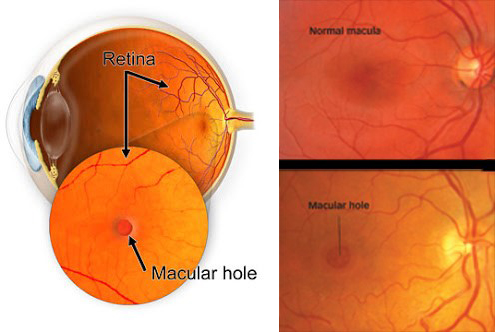

O buraco macular é uma alteração no centro da mácula causada pela tração tangencial do tecido perimacular. Não se sabe porque algumas pessoas desenvolvem esta tração. É mais comum entre as mulheres e em pessoas com mais de 40 anos.

Os sintomas são distorção da visão central associado a um escotoma (mancha) escuro, arredondado e central.

O diagnóstico é feito através do mapeamento da retina (fundo de olho) e da tomografia da retina (OCT).